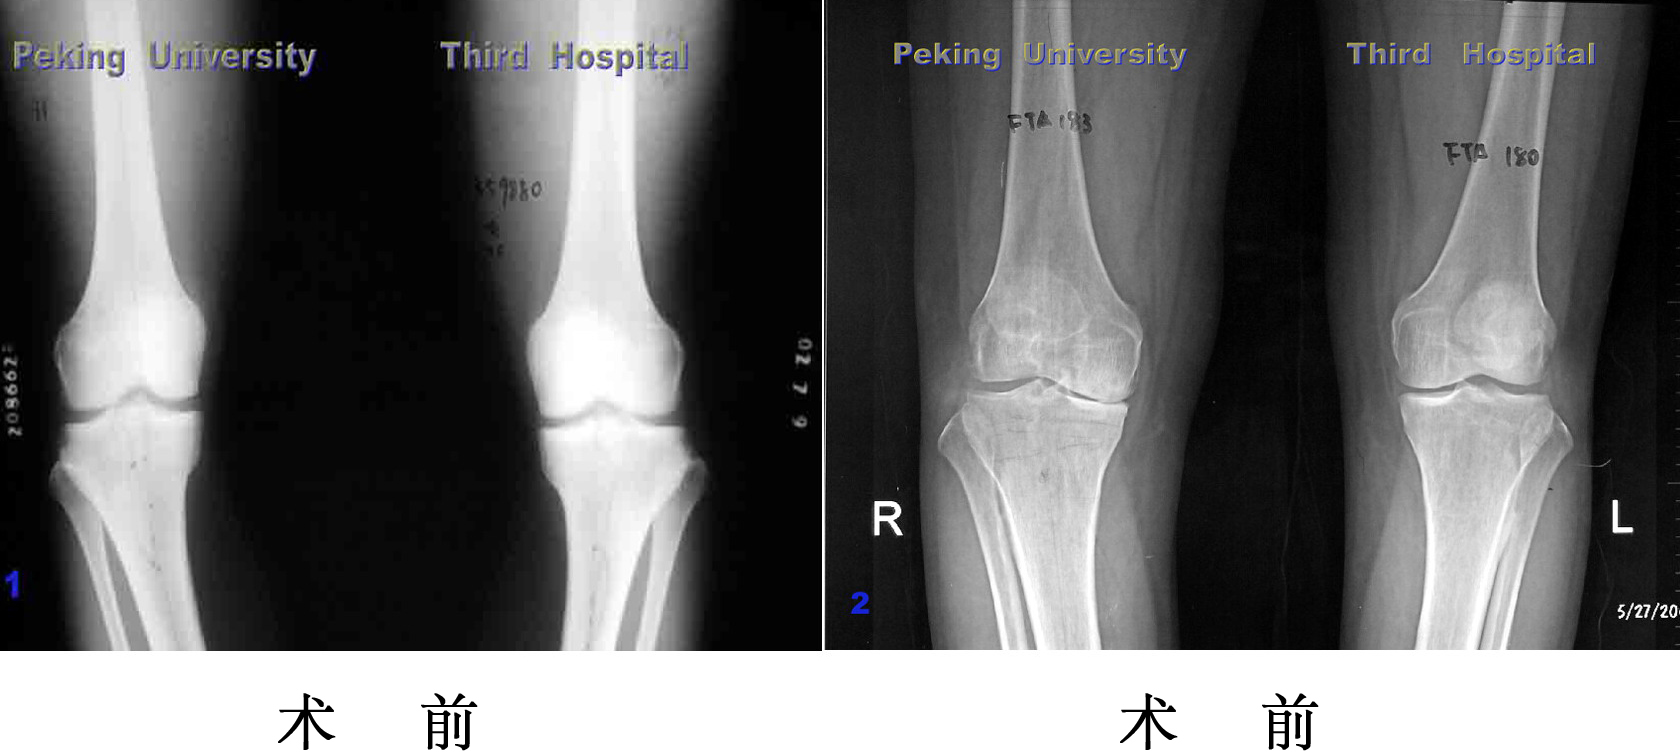

胫骨截骨

胫骨植骨

严重膝内翻,胫骨平台内侧植骨,软组织松解,术后内翻纠正

内 翻